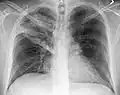

Normal AP CXR

Normal lateral CXR -